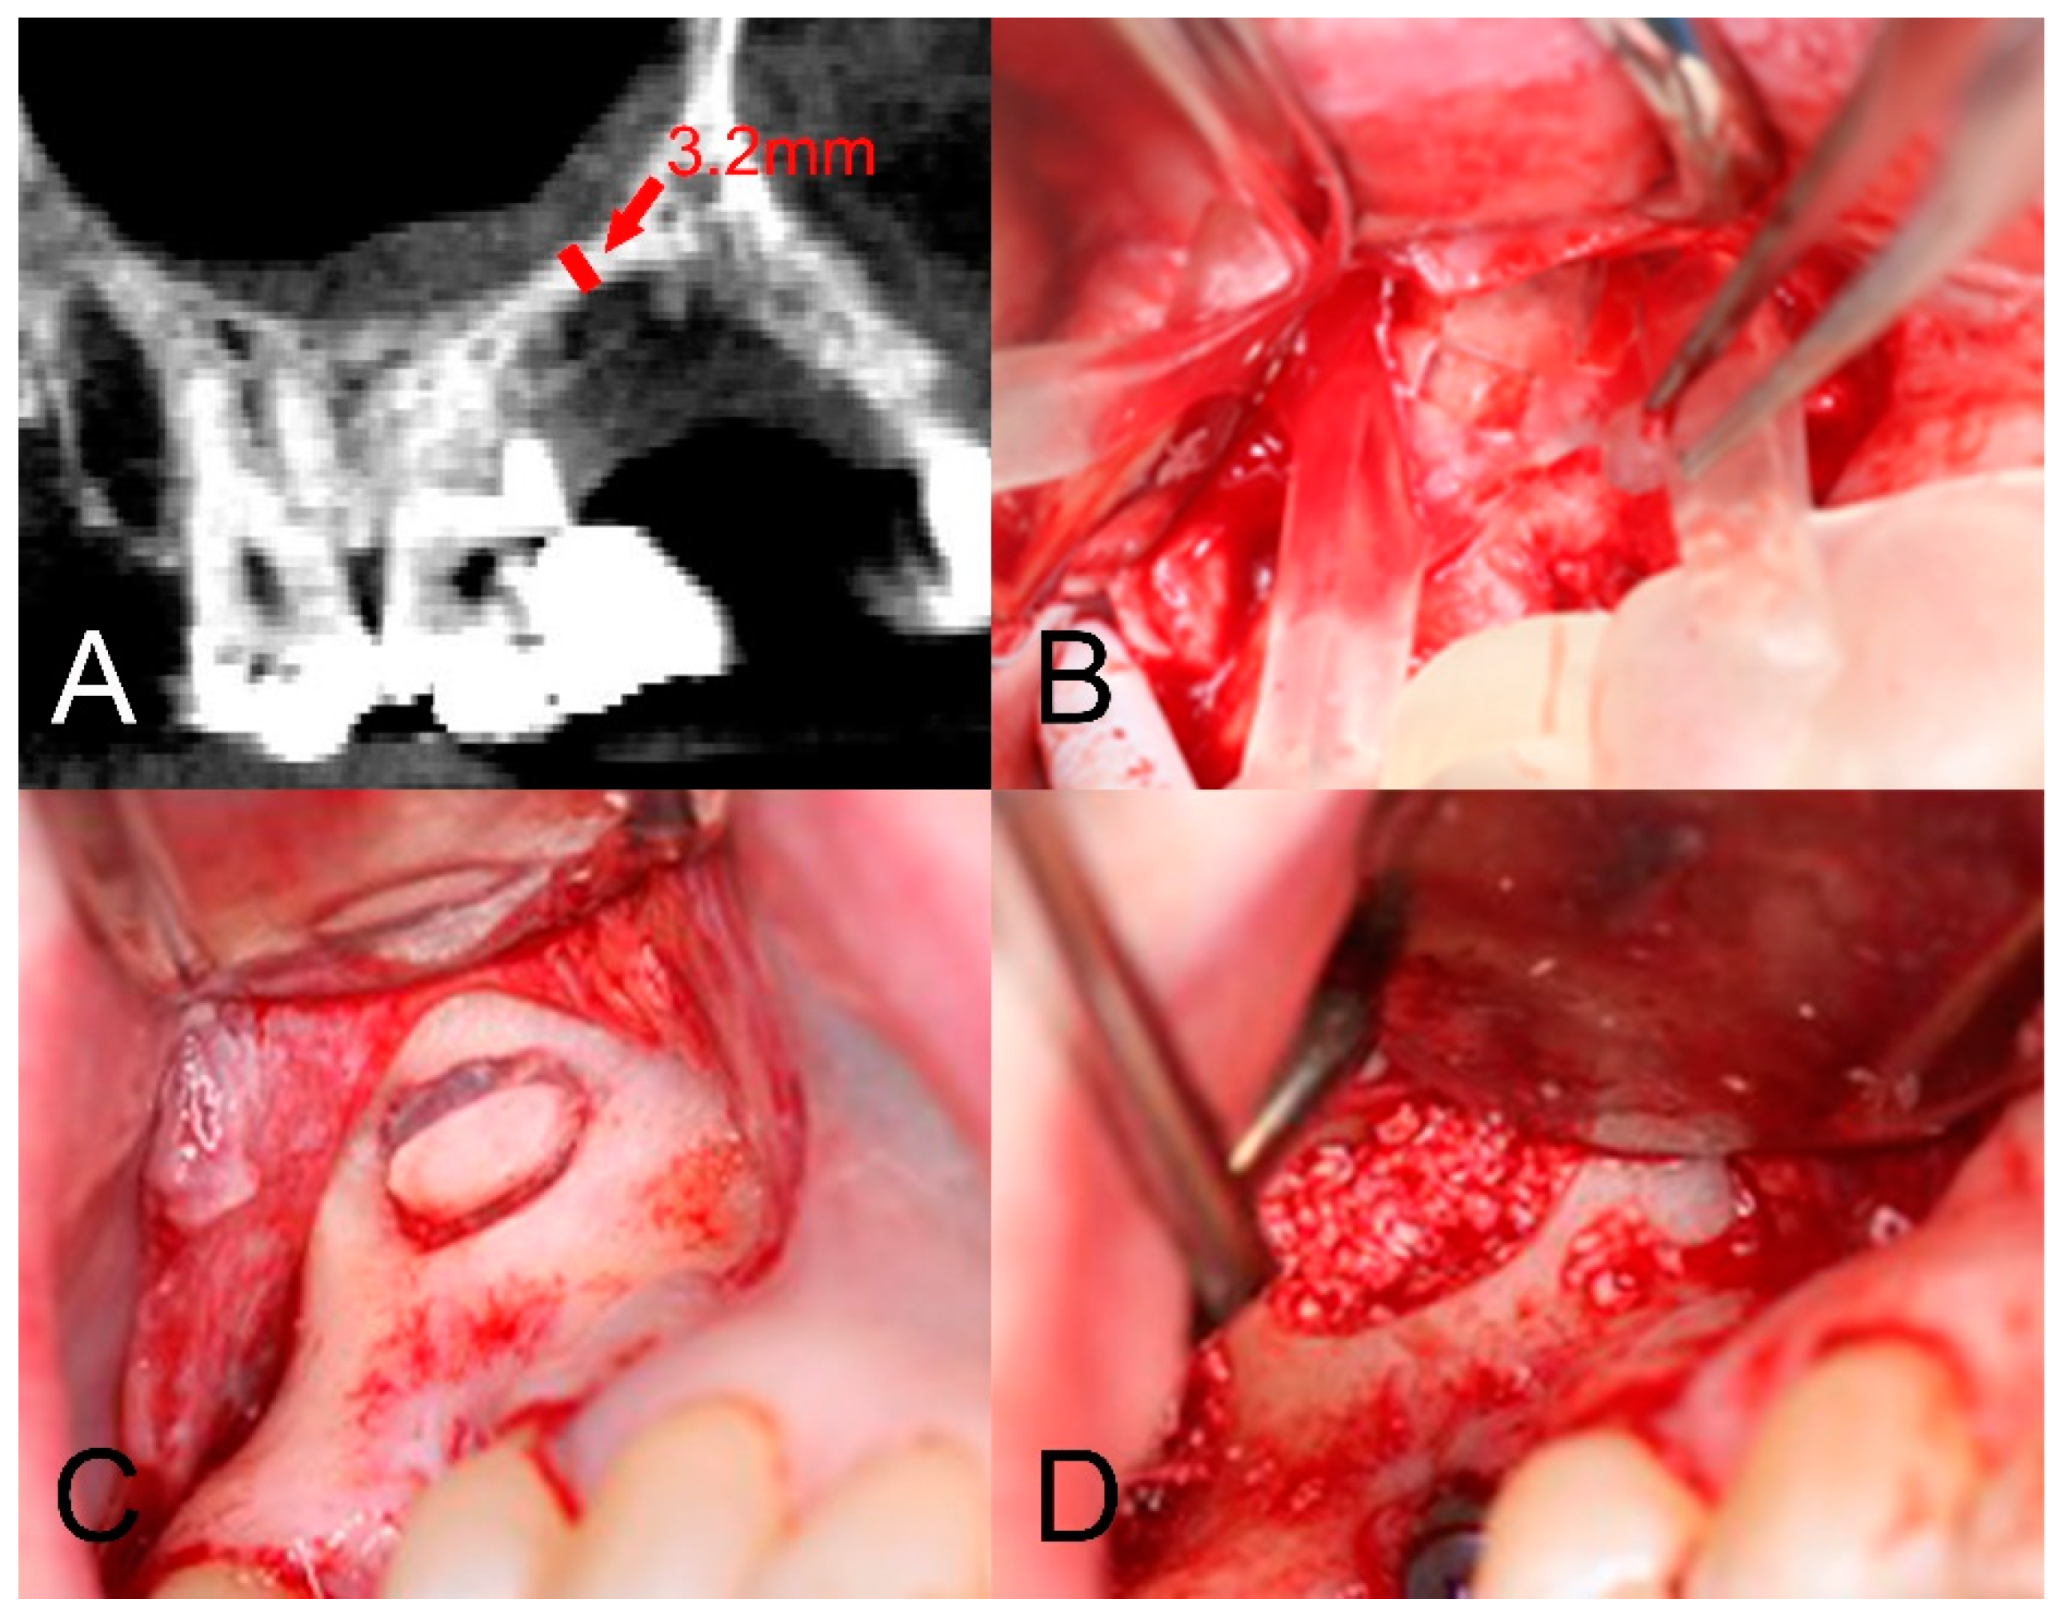

2.2. Case 2: Precision Osteotomy

A 49-year-old male patient presented requesting restorative options for a missing 23. A dental implant was proposed as a treatment option, and the patient consented to proceed. During screening with OPG and CBCT, a submerged radiopaque GP was observed. The GP intersected the ideal implant position (Figure 5A). It was decided that it would be removed utilising a surgical guide to minimise cortical plate loss for bone preservation prior to implant placement. The treatment plan was discussed with the patient, and informed consent was obtained. Local anaesthesia with 4% articaine containing 1:100,000 adrenaline was administered via buccal, palatal, and mid-crestal infiltrations. A mid-crestal incision and vertical relieving incisions were performed. A full thickness periosteal flap was raised at the left canine region to expose the alveolar ridge. The surgical guide was placed over the exposed ridge to indicate the position of the retained GP and subsequent corticotomy. A Ø 1.4 mm small round bur was then inserted through the surgical guide channel to remove the cortical plate to reveal the GP (Figure 5B). The GP was removed with a small spoon excavator, and a periapical radiograph was taken to ensure the complete removal of restorative debris (Figure 5C). The width of the osteotomy site was 3 mm at the apical end and 2 mm at the coronal end (Figure 5D). The Bio-Gide membrane (Geislitch) was placed over the osteotomy site to prevent soft tissue growth into the defect and enable fibroblast attachment for the formation of new bone tissues and blood vessels in the defect. No bone substitute material was used. The flap was repositioned and secured with six simple interrupted sutures using PROLENE suture 5-0 (Ethicon). The surgical site was reviewed at 6 and 12 months post-operatively, with intraoral radiographs confirming the complete removal of the GP (Figure 6).

Figure 5. The use of the surgical guide in a precision osteotomy: (A) implant planning showing a foreign body intersecting the proposed implant site; (B) surgical guide in situ being used to guide the corticotomy; (C) removal of the foreign body; (D) osteotomy site with a periodontal probe indicating the dimensions of the bone removed.